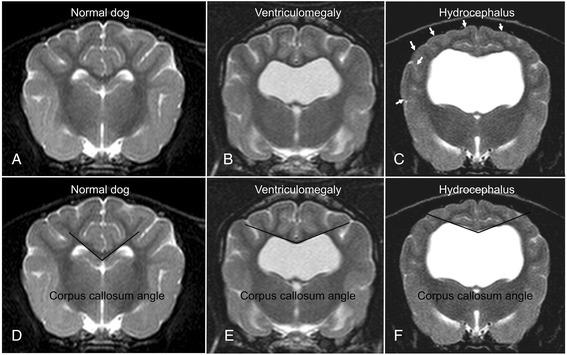

Magnetic resonance imaging (MRI) findings of canine brains with enlarged ventricles in asymptomatic dogs were compared to those in dogs with clinically relevant internal hydrocephalus, in order to determine the imaging findings indicative of a relevant increase in intraventricular pressure. Discrimination between clinically relevant hydrocephalus and ventriculomegaly based on MRI findings has not been established yet and is anything but trivial because of the wide variation in ventricular size in different dog breeds and individuals. The MRI scans of the brains of 67 dogs of various breeds, skull conformation and weight were reviewed retrospectively. Based on clinical and imaging findings, the dogs were divided into three groups: a normal group (n = 20), a group with clinically silent ventriculomegaly (n = 25) and a group with severe clinically relevant internal hydrocephalus (n = 22). In addition to the ventricle/brain-index, a number of potential subjective signs of increased intraventricular pressure were recorded and compared between the groups.

The ventricle/brain-index was significantly higher in dogs with relevant hydrocephalus (p < 0.001) and a threshold value of 0.6 was specified as a discriminator between internal hydrocephalus and ventriculomegaly. Other MR imaging findings associated with clinically relevant hydrocephalus were an elevation of the corpus callosum (p < 0.01), dorsoventral flattening of the interthalamic adhesion (p < 0.0001), periventricular edema (p < 0.0001), dilation of the olfactory recesses (p < 0.0001), thinning of the cortical sulci (p < 0.0001) and/or the subarachnoid space (p < 0.0027) and disruption of the internal capsule adjacent to the caudate nucleus (p < 0.0001).